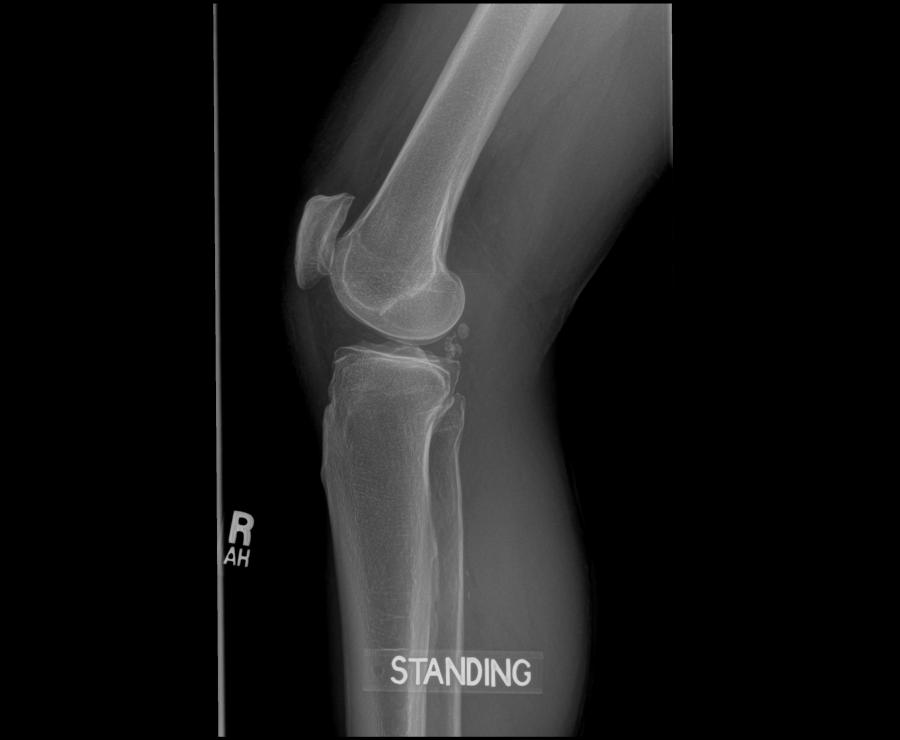

Before – Right Knee

Before – the right kn ee